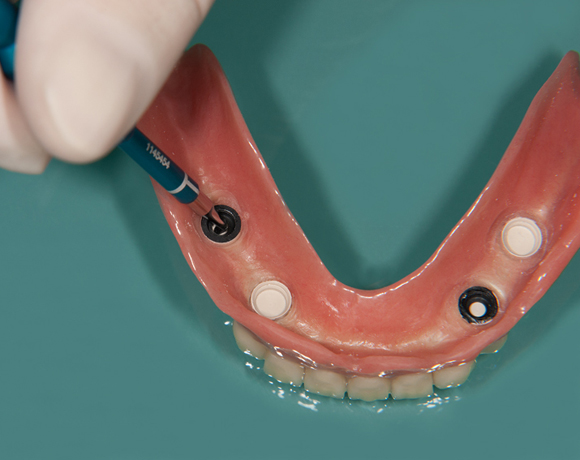

Fixierung einer Unterkiefervollprothese mit vier Implantaten

Mit Implantaten und dem Locatorsystem lassen sich Prothesen gut fixieren und geben einen guten Halt zum Essen und Sprechen

61 jähriger Patient, im Ober- und Unterkiefer mit Vollprothesen versorgt. Der Patient litt darunter, dass seine Unterkieferprothese keinen richtigen Halt hatte. So wurde ihm vorgeschlagen mit vier Implantaten und dem Locatorsystem die Prothese am Unterkiefer zu fixieren und damit einen hohen Komfort beim Essen und Sprechen zu ermöglichen. Der Patient entschied sich für eine metallfreie Versorgung. Es wurden Zeramex® P Implantate von Dentalpoint AG verwendet, für die Matrizen das System der Fa. Valoc das Novalocsystem gewählt. Die Verstärkung der Prothese wurde metallfrei mit einem PEEK – Gerüst gewährleistet.